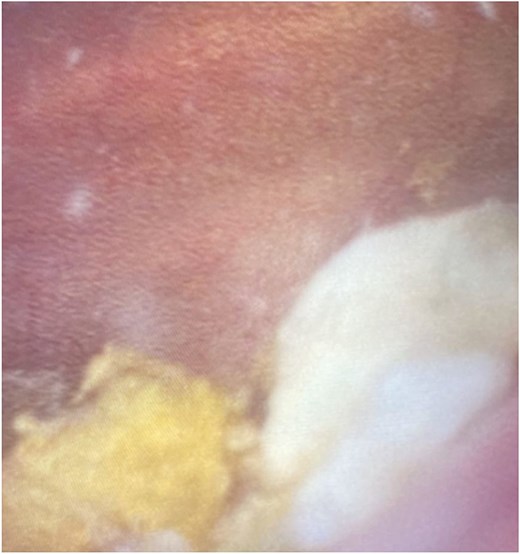

The patient was managed surgically with scrotal exploration and left orchidectomy. Intra-operatively the superior pole of the testis was necrotic, with pus within the ruptured tunica albuginea. Cystoscopy demonstrated faeculant debris within the bladder (Fig. 3). Post-operatively he recovered well and was discharged on day two with a prolonged course of intravenous antibiotic therapy in the community.

Cystoscopy image demonstrating significant faeculant debris within the bladder mucosa.